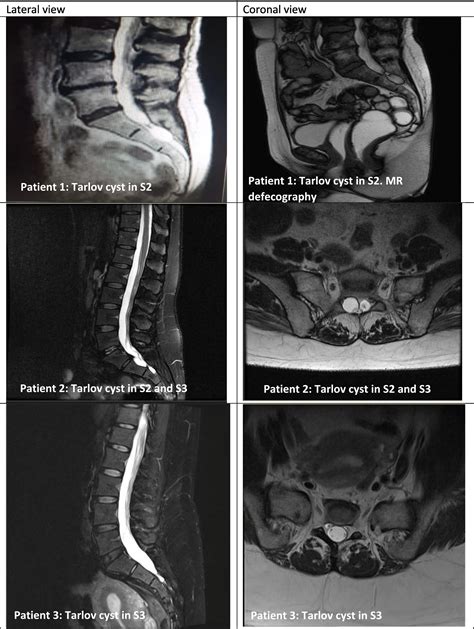

A Sacral Tarlov Cyst, also known as a perineural cyst, is a cerebrospinal fluid-filled sac that develops at the junction of the dorsal root ganglion, most commonly in the sacral region—the triangular bone at the base of the spinal column. These cysts are formed when cerebrospinal fluid (CSF) enters the nerve root sheath and becomes trapped, creating a structural abnormality that can press against the delicate nerve fibers housed within the spinal canal.

Because these cysts often remain asymptomatic, they are frequently discovered incidentally during diagnostic imaging, such as an MRI or CT scan performed for an unrelated reason. However, when they grow in size or exert significant pressure on the surrounding nerves, they can lead to a variety of symptoms that mimic other spine-related conditions, making an accurate diagnosis essential.

Diagnosing a symptomatic Sacral Tarlov Cyst requires a comprehensive approach. Because they are soft-tissue structures, they are best visualized using high-resolution Magnetic Resonance Imaging (MRI). A radiologist or neurosurgeon will look for specific markers, such as the location, size, and the degree of bone remodeling (erosion) occurring in the sacrum, which indicates that the cyst has been present for a significant period.

In addition to imaging, physicians may conduct a detailed neurological examination to map out sensory deficits and assess muscle strength. Some clinics may also utilize specialized imaging, such as a Cine-MRI, to study the flow of cerebrospinal fluid around the cyst.